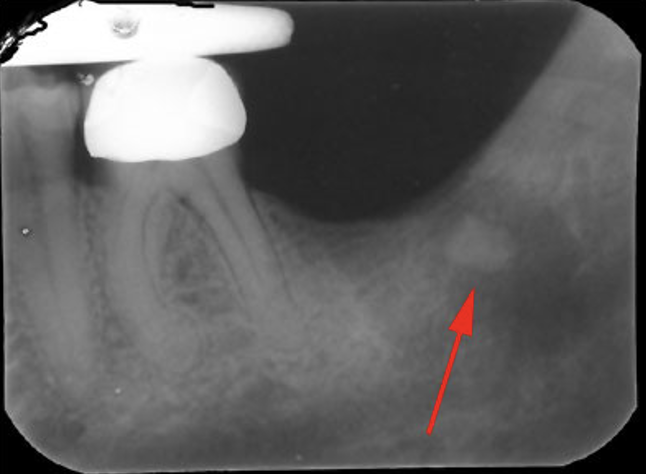

<p>what stands out about this bitewing</p>

what stands out about this bitewing

• there should be a root fill between the end of the post-crown on the LR5 but it is missing

<p>what does the red arrow represent</p>

what does the red arrow represent

• retained root from an extraction